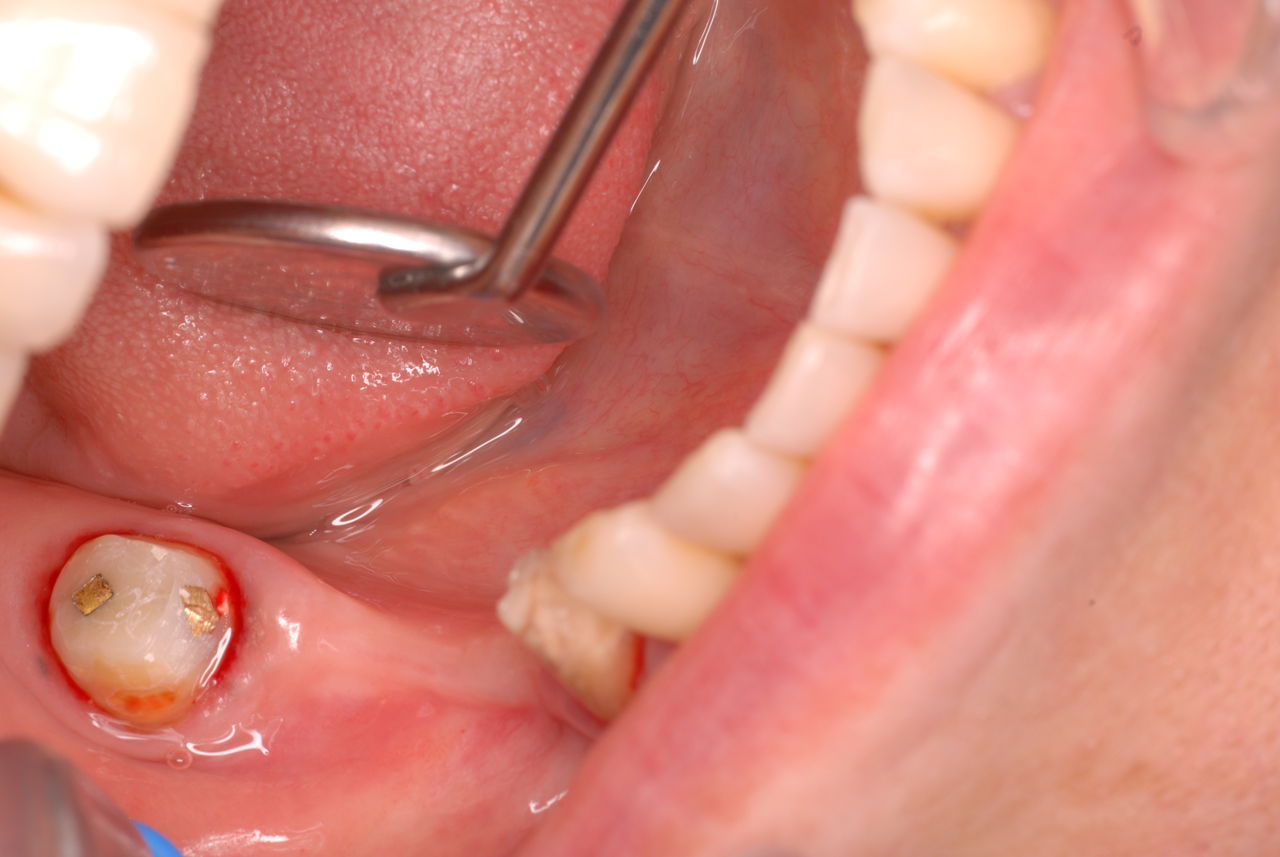

今日のすべての患者さんは、一人を除いて新患を含めてすべて歯周病の方でした。

歯周病は殆どの方に存在し、気づかないうちに進行していきます。

そして場所や痛みなどの症状がはっきりしないのです。冷たい水がしみることもあります。